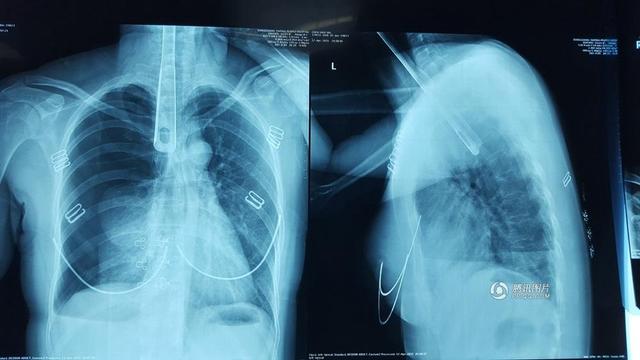

女子为止喉痒将30厘米长锅铲捅进食道

广东省东莞市虎门镇一30多岁的陈女士在家炒菜,突然觉得喉咙堵得难受,好像里面有个很大的“疱”。她先是用手指往喉咙里抠,

抠不着,又用筷子去捅,筷子还是不够长。她于是拿起炒菜用的30多厘米长的铝合金锅铲,用锅铲把手往喉咙里捅了进去……